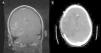

Caso 2. Adolescente de 16 años que ingresa en la UCI por fluctuación del nivel de consciencia en contexto de encefalitis. Consulta por fiebre, cefalea y diplopía. La TC muestra hipodensidad temporal derecha. El análisis del LCR fue normal, aunque con PCR a virus herpes simple tipo 1 (VHS-1) positiva. A las 24 horas inicia disminución del nivel de consciencia; se repite la TC que objetiva lesión temporal derecha cortical e importantes signos de edema cerebral e incipiente herniación (fig. 1A). Se coloca un sensor de PIC intraparenquimatoso que evidencia presiones de 30mmHg sin respuesta a medidas farmacológicas, por lo que se practica CD con apertura de la duramadre y buen control posterior de la PIC. A los 7 días se extuba y mantiene el nivel de consciencia conservado. La RM muestra cambios evolutivos secundarios a encefalitis herpética con abombamiento del parénquima a través de la craniectomía y mejoría de la compresión sobre el sistema ventricular (fig. 1B). Completa 21 días de tratamiento con aciclovir. Como secuelas neurológicas al alta destaca hemiparesia izquierda leve, paresia del sexto par craneal bilateral y epilepsia bien controlada con carbamazepina. A los 6 meses se realiza craneoplastia sin incidencias (fig. 2). Pasados 9 meses tras el ingreso, la paciente presenta una resolución de la hemiparesia y el estudio cognitivo es normal (leve déficit de memoria inmediata y comprensión lectora).